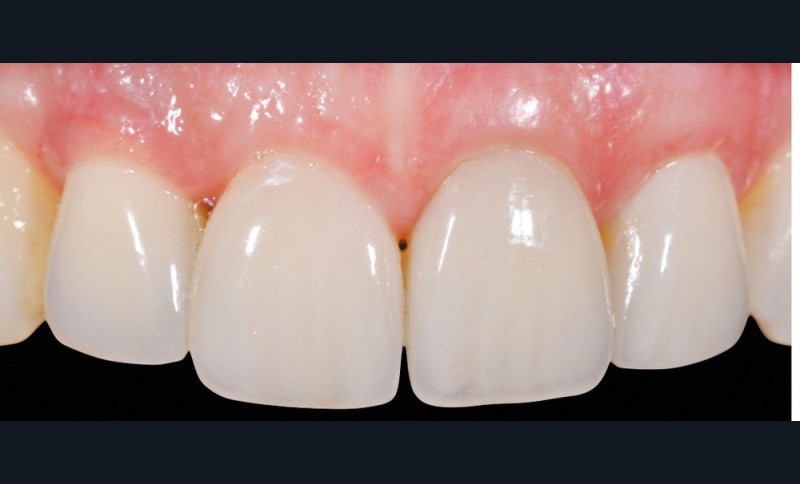

Le scellement de restaurations sur des piliers implantaires demeure une solution très intéressante (fig. 1). Cette technique reprend en effet les standards de la prothèse sur dent naturelle, à savoir un pilier implantaire (faux-moignon) vissé dans l’implant sur lequel est scellée une coiffe prothétique. Ses principaux atouts sont de corriger facilement les axes implantaires s’ils sont divergents par rapport à ceux des couronnes, tout en masquant l’émergence de la vis du pilier et conservant ainsi les faces occlusales intactes.

La seconde complication, plus grave, est le risque d’oublier des excès de ciment au niveau sous gingival. Ces derniers sont la cause principale avérée des péri-implantites et des pertes osseuses (fig. 2). Il est donc nécessaire de prendre toutes les précautions pour limiter au maximum ce risque.